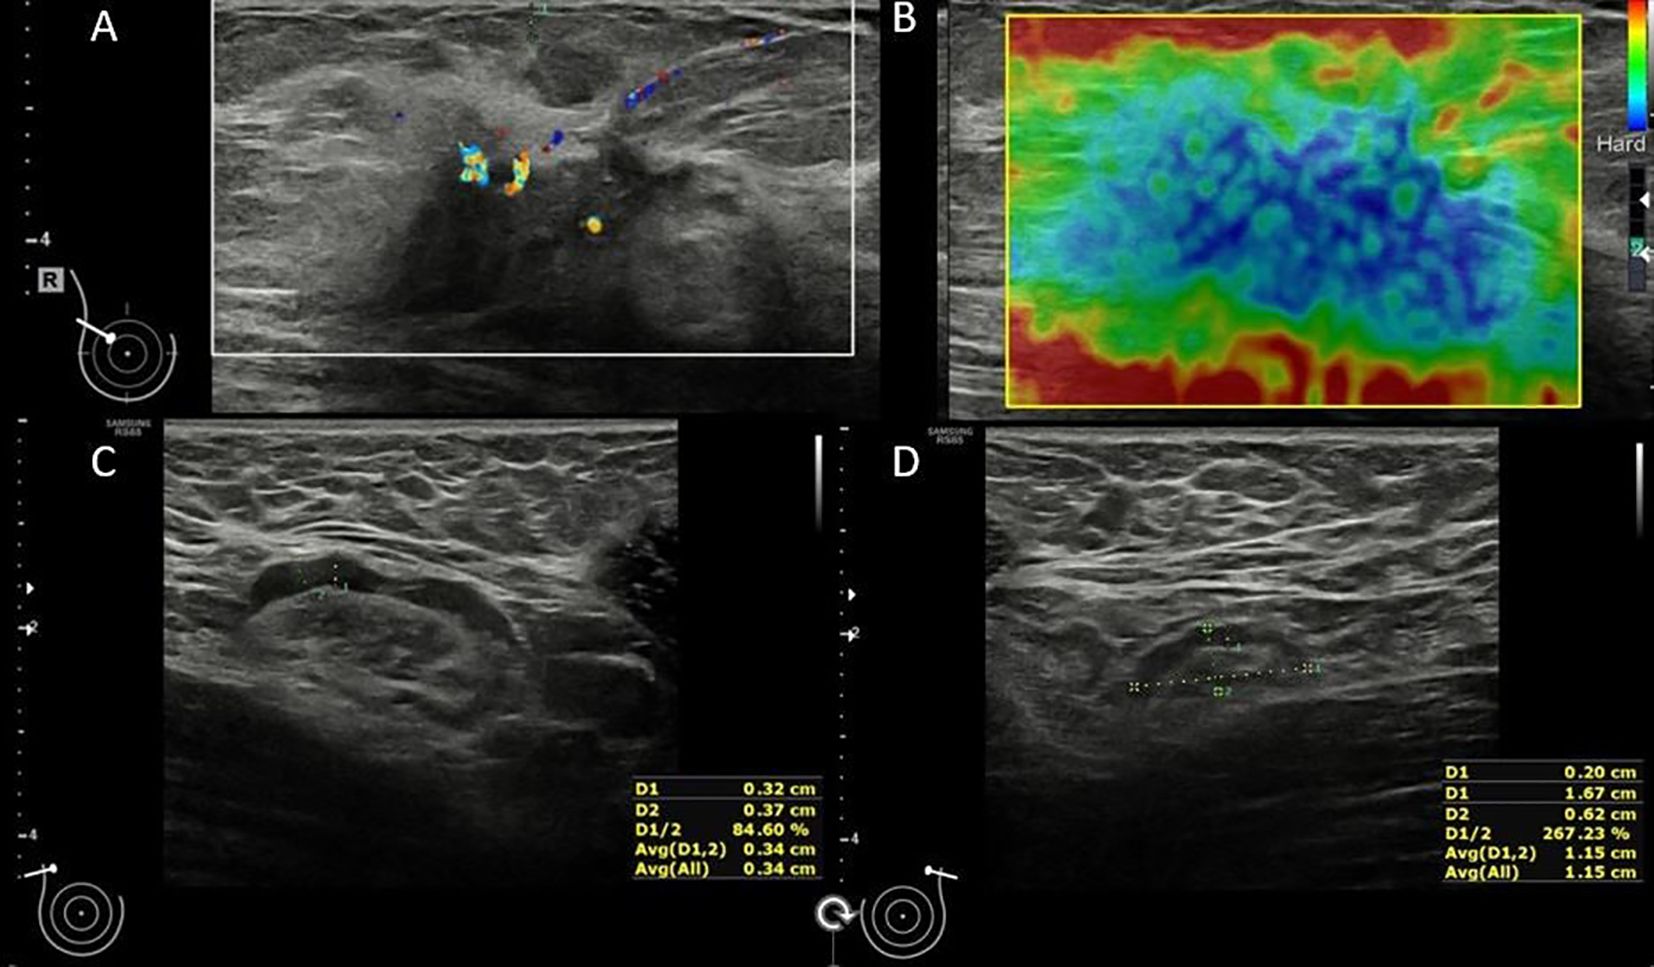

Background: Accurate axillary lymph node assessment is critical in breast cancer staging. This study aimed to evaluate whether ultrasound (US)-based measurements, particularly cortical thickness and comparison with contralateral lymph nodes, could improve diagnostic accuracy in detecting axillary metastasis. Methods: In this prospective study, 110 breast cancer patients underwent bilateral axillary US. Ipsilateral and contralateral lymph nodes were assessed for shape, size, cortical characteristics, and hilum preservation. Quantitative features were compared between metastatic and non-metastatic nodes. Diagnostic accuracy was evalu-ated using ROC analysis, and various cut-off values were tested. Results: Metastatic nodes showed significantly increased cortical thickness (median 7.5 mm vs. 2.1 mm, p<0.001), larger short axes, and irregular shapes. The cortical thickness of ipsilateral lymph nodes had an AUC of 0.967 with a 3.4 mm cut-off yielding 97.7% sensitivity and 89.1% specificity. Comparing ipsilateral and contralateral cortical thickness revealed a 2.05 mm difference as optimal (AUC 0.926, 86% sensitivity, 89.1% specificity). US-based assessment outperformed traditional imaging in accuracy (92.66% vs. 82.73%). Conclusions: Quantitative US assessment of axillary lymph nodes, especially cortical thickness and bilateral comparisons, enhances diagnostic accuracy in breast cancer. Integrating these measures may reduce unnecessary biopsies and improve staging efficiency.